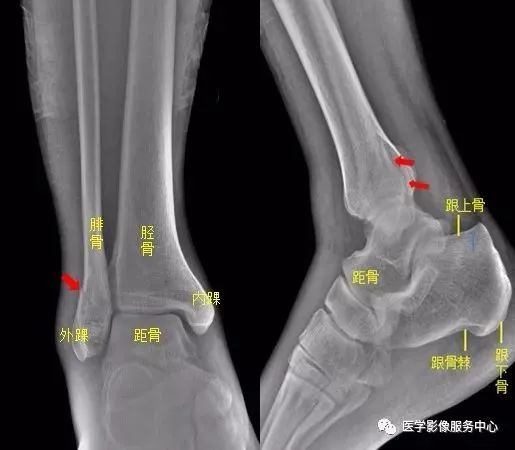

(十)踝关节

右侧外踝骨皮质连续中断,可见透亮骨折线影,可见软组织稍肿胀影,右踝关节骨折。

Warmreminder:踝关节扭伤,许多大夫只做踝关节正侧位。有时踝关节正侧位不能看出有明显异常,而有局部软组织肿胀,活动受限时,根据我的经验,踝关节扭伤有时只做正侧位是有局限性的;小妙招:足正位也是必不可少的。

此患者就是踝关节扭伤,踝关节正侧位未见异常,加拍足正位时发现外踝骨折。

所示右侧腓骨远端见斜行骨折线,骨折端对位对线尚可,右腓骨远端骨折。